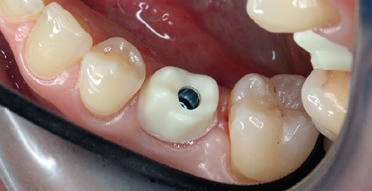

Nach der geführten Implantatbettaufbereitung wurde das Astra Tech Implant System EV 4,8C × 13 mm durch die Hülse hindurch mit Höhenanschlag in seine geplante Position inseriert (Eindrehmoment final: 45 Ncm) (Abb. 8 bis 10). Die Lage des Implantats wurde mit einer intraoralen Röntgenaufnahme postoperativ überprüft (Abb. 11). Es folgte die digitale Abformung mit der CEREC Omnicam: Um die Implantatposition exakt zu übertragen, wurde ein Scanbody platziert (Abb. 12). Der dabei erzeugte Scan wurde für das präzise Design eines Provisoriums mit der Abformung des Milchzahnes überlagert und im Anschluss gefräst (Abb. 13). Das Kunststoffprovisorium wurde mit der dazugehörigen TiBase verklebt (Multilink Hybrid Abutment, Ivoclar Vivadent). Zuvor wurden sowohl die TiBase als auch das Zirkonabutment sandgestrahlt, im Ultraschallbad gereinigt und im Anschluss silanisiert (Monobond plus, Ivoclar Vivadent). Im nächsten Schritt wurde das Provisorium mit dem Implantat okklusal verschraubt (Abb. 14) und mit Komposit verschlossen (Abb. 15 bis 17). Um eine Überbelastung des Implantats während der Einheilzeit zu vermeiden, war eine Nonokklusion von 0,5 bis 1 mm zum Antagonisten zu beachten. Dazu gehörte auch die Empfehlung an die Patientin, das Provisorium in den ersten Monaten nur eingeschränkt zu belasten (weiche Kost).

Nach einer Einheilzeit von 3 Monaten wurde die Osseointegration röntgenologisch kontrolliert, das Provisorium über ein okklusales Re-Opening entfernt und anschließend die Implatatposition mit dem Intraoralscanner CEREC Primescan von Dentsply Sirona und der CEREC SW 5 erneut gescannt.